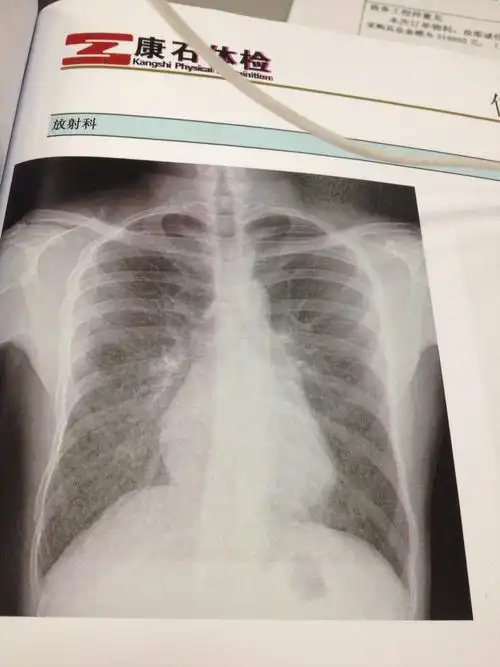

胸透检查

胸片的胸片作用

胸透照片,医生请进,报告上说脊柱向左侧凸,请问是否正常.